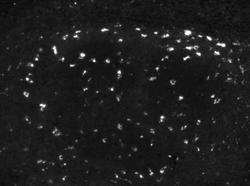

NBP1-04278 IHC

Full details

Method:

Other validation